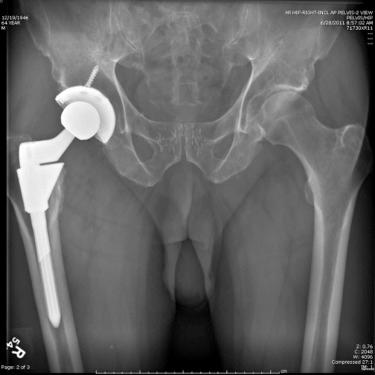

Continuous radiolucencies were seen in Gruen zones 1, 2, 6, and 7 on anteroposterior radiographs ( Fig. 62.1, A ) and zones 8 and 9 on lateral radiographs ( Fig. 62.2, B ). A pedestal was seen near the distal lateral cortex at the tip. Thus, radiographs were suggestive of failure of osseous integration of the primary stem.

FIGURE 62.1, A, Preoperative hip anteroposterior radiograph shows failed osteointegration of the stem. B, Preoperative hip lateral radiograph (false-profile view).

FIGURE 62.2, Postoperative anteroposterior radiograph of the pelvis shows revision with Emperion stem.

Patient underwent revision THA due to persistent functional restriction and thigh pain. Explantation of the femoral implant resulted in a type I Paprosky bone loss, making it difficult for a larger primary-tapered wedge stem to obtain stable fixation in the meatphysis. Emperion stem was used to achieve adequate fit and fill in the meatphyseal and diaphyseal regions. Restoration of offset, leg-length, and stable fixation were achieved with the use of an Emperion stem (see Fig. 62.2 ). Patient reported subsequent resolution of symptoms and improvement of functional activity. The principles of revision surgery with this type of stem are discussed here.